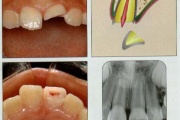

Põhimõtted – Trauma tagajärjel irdunud jäävhammast tasub alati tagasi istutada, kui õnnetuses on hammas ja alveool terveks jäänud. Kui ka hammas hiljem kaotataks, on istutamine tähtis, sest see kergendab implanteerimist ja lükkab edasi hamba asendamist proteesiga. – Mingil juhul ei Loe edasi »